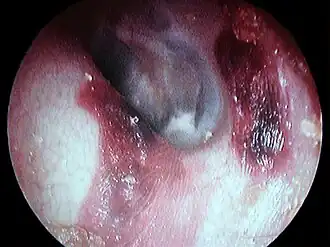

Hématome du conduit auditif externe gauche post coton tige